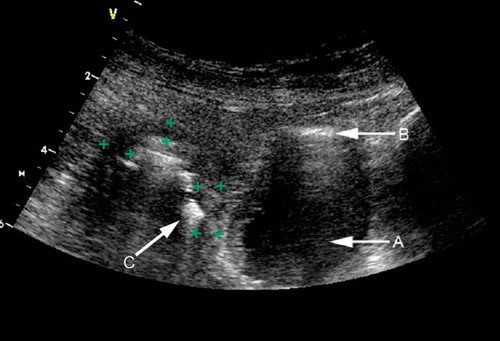

Ulcerøs kolitt lokalisert til rectum kan være vanskelig å påvise med transabdominal ultralyd. Man kan følge colon fra sigmoideum til coecum med ultralyd og således påvise om det foreligger sigmoiditt, venstresidig kolitt, subtotal- eller totalkolitt. Siden affeksjonen vanligvis er kontinuerlig fra rectum og videre proksimalt ved ulcerøs kolitt, er det lettere å kartlegge utbredelsen enn ved Crohns sykdom der sykdommen kan være lokalisert til flere atskilte områder i en ellers normal tarm. Ved ulcerøs kolitt finner man vanligvis ikke veggtykkelse over 6 mm ved transabdominal ultrasonografi (15), og lagdelingen i tarmveggen er ofte bevart (11). Dette kommer av at inflammasjonen som regel ikke går lenger inn i tarmveggen enn til submucosa. Lag 2 og 3, som hovedsakelig svarer til henholdsvis mucosa og submucosa, er ofte fortykket ved ulcerøs kolitt (11) (fig 2). Ved mild og overflatisk Crohns sykdom kan man noen ganger gjøre tilsvarende funn med bevart lagdeling og mindre uttalt veggtykkelse.

Stenoser kan forekomme ved Crohns sykdom (fig 3). Man ser da ofte betydelig fortykket vegg og avsmalnet lumen og en prestenotisk utvidelse. Den fortykkede tarmveggen i stenosen har liten eller ingen motilitet. Bortfall av lagdeling i stenosen indikerer ødem i tarmveggen og sannsynlig akutt inflammasjon, mens mer bevart lagdeling kan indikere fibrose (18). Det er viktig for valg av behandling å vite om den fortykkede veggen i en stenose skyldes hovedsakelig aktiv inflammasjon eller fibrose. Ved aktiv inflammasjon kan pasienten ha nytte av medisinsk behandling, mens kirurgi vanligvis er indisert ved kroniske betennelsesforandringer og fibrose (18). Hvis man ved hjelp av fargedoppler ser rikelig med kar i stenoseområdet, tolkes det som et uttrykk for inflammatorisk aktivitet. Da kan medikamentell behandling være verdt å forsøke. Ultralyd er i flere studier brukt til å påvise stenoser hos pasienter med Crohns sykdom. I disse studiene har ultralyd en sensitivitet på 74 – 100 % og en spesifisitet på 91 – 100 % (9, 14, 19).